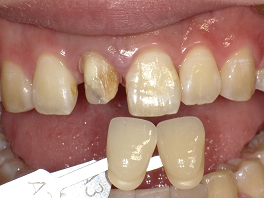

3人目の方も30台の女性の方です。右の一番前の歯が黒いことを気にして来院されました。

この方は、セラミックの歯を被せてほしいということで来院されましたが、グラディアダイレクトは歯を削る必要がないことを説明すると、歯を大切にしたいという思いで、グラディアダイレクトをすることになりました。

術前 ↓

術後

本人の希望で少し白めに仕上げています。この後にホワイトニングをすると回りの歯も白くなってさらに良くなるでしょう。